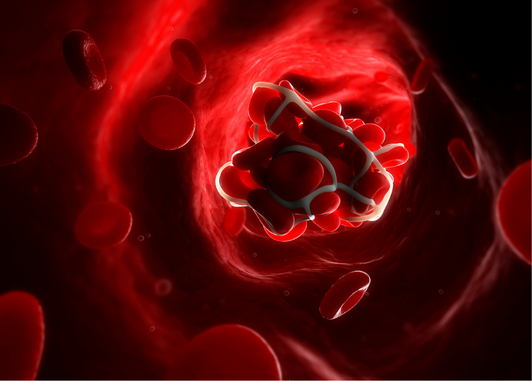

Even before becoming the standard of care in large-vessel occlusion ischemic stroke, mechanical thrombectomy has offered a potential insight into stroke etiology, by means of direct thrombus analysis.

Extracted thrombi were frequently classified as either erythrocyte-rich (or “red thrombi”), fibrin and platelet-rich (or “white thrombi) or mixed, as they appeared under light microscopy.1,2 One of the first studies aiming to predict thrombus composition based on initial imaging was the study conducted by Liebeskind et al., which found that thrombi presenting with a hyperdense MCA sign on plain CT or with a susceptibility vessel sign on susceptibility weighted-imaging MRI contained a significantly higher concentration of erythrocytes.1 This finding was confirmed by a more recent meta-analysis, demonstrating higher odds of erythrocyte-rich thrombi if a hyperdense artery sign was present.3

In a landmark study on over 1300 patients, the authors demonstrated a higher mean concentration of red blood cells in thrombi extracted from patients with large-artery atherosclerosis versus cardioembolic strokes. Fibrin and platelet concentrations were otherwise similar. The highest erythrocyte concentration was identified in thrombi resulting from vessel dissection. However, no definite threshold could be estimated on the ROC analysis for differentiating between the two main stroke etiologies.5

Regarding acute stroke treatment, recanalization rate seems to be associated with thrombus type. In a recent review,4 the authors conclude that erythrocyte-rich thrombi are associated with higher recanalization rates following endovascular treatment and intravenous thrombolysis, supposedly as a result of their increased sensitivity to tissue plasminogen activator. On the contrary, fibrin-rich thrombi are generally considered more refractory to acute treatment, because of their superior stiffness and adherence.

Lastly, thrombus composition varied dynamically with each thrombectomy pass. In a study conducted by Fitzgerald et al.2, per-pass analysis revealed that erythrocyte concentration was highest in earlier passes and decreased afterwards; moreover, platelet and fibrin concentration was higher in later passes. The latter might either reflect the superior adhesiveness of fibrin-rich thrombi (requiring a higher number of passes) or the preferential fragmentation of the thrombi along the interface between erythrocyte predominant areas and fibrin-rich areas.

In conclusion, while imaging may predict thrombus histology and recanalization success (in terms of “red” versus “white” clot), thrombus analysis by regular staining does not provide sufficient information to discern between large-artery atherosclerosis and cardioembolic stroke types. While initial thrombus composition might be specific to the site of formation, its persistence in the circulation, embolization and fragmentation will most likely alter its structure afterwards. This limitation might potentially be overcome by using more advanced analysis techniques in future studies.